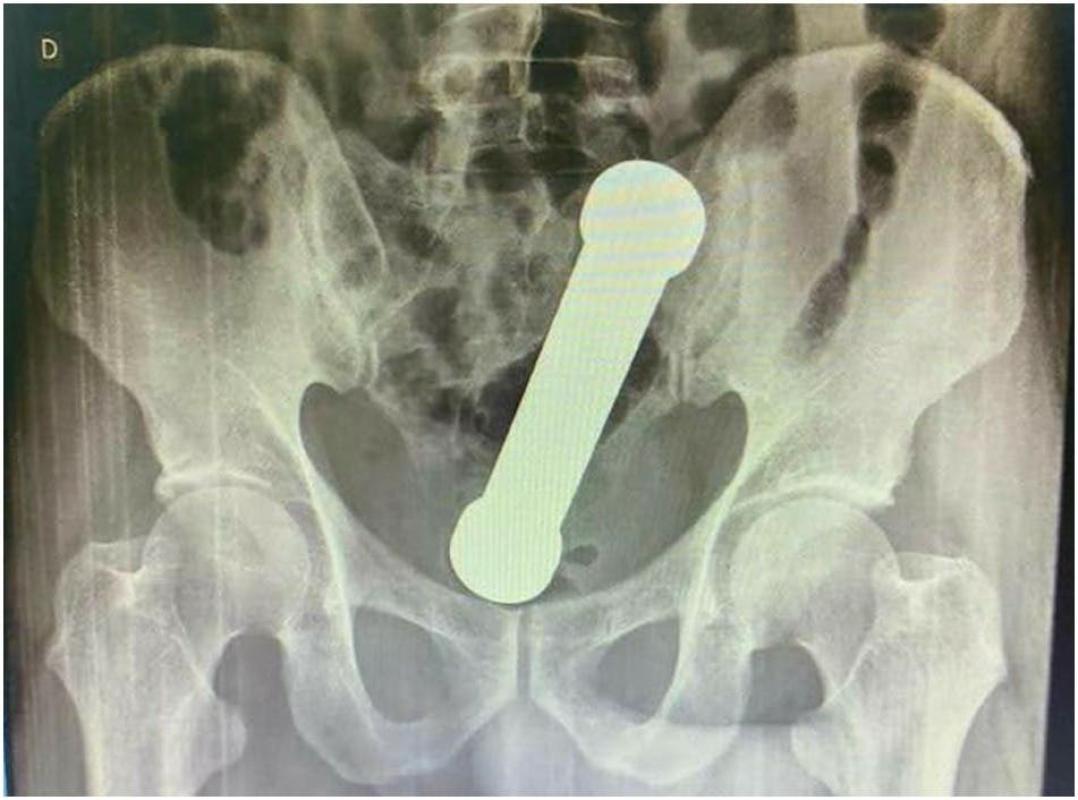

Un equipo médico extrajo una mancuerna del interior de un paciente en Manaus, Brasil, quien se habría introducido el objeto con motivos sexuales.

El caso fue registrado en Brasil, en donde un sujeto de 54 años concurrió a un recinto asistencial debido a que tenía un dolor de estómago, vómitos y estitiquez. Durante el chequeo médico inicial, el paciente se mostró reticente a cooperar con los funcionarios.

Las radiografías abdominales revelaron que el hombre tenía una mancuerna de 20 centímetros atorada a la altura del lugar en que el colon se conecta con el recto.

De acuerdo a lo confesado por el sujeto, dos días atrás se había introducido la pesa metálica de dos kilos por motivos sexuales. Lamentablemente, después no pudo extraer el objeto de su interior.

El equipo médico intentó extraer el objeto mediante el uso de anestesia y pinzas quirúrgicas, pero las mancuernas no cedían. Por lo anterior, uno de los encargados tuvo que proceder a una “extracción manual”, introduciendo su antebrazo en el hombre.

Luego de tres días de hospitalización y sin complicaciones post extracción, el paciente fue dado de alta.